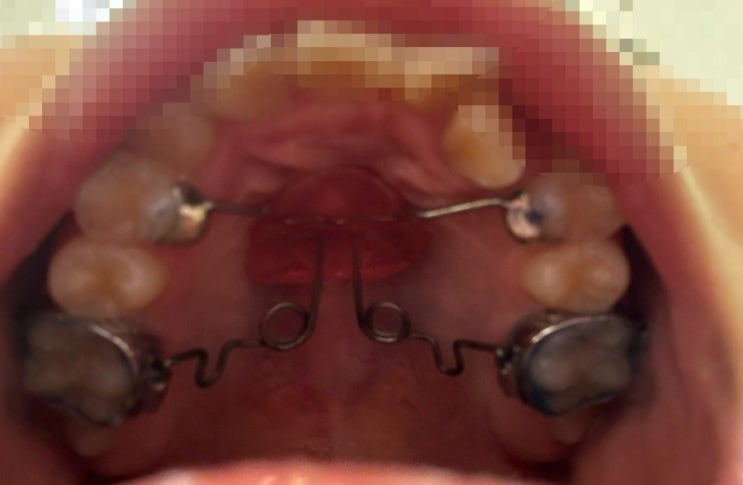

악궁을 확장한지 3개월 만에 이 두 개가 들어갈 만큼 자리가 생겼다. 교수님 면담 예정이라 기대를 했는데,...

[세브란스 치과병원 교정 2,3,4] 교정 시작은 치아 사이 벌리기부터

이를 빼지 않고 진행하기로 했으나 공간이 없는 상황.. 이 사이사이를 벌리고 이를 어금니 쪽으로 이동시키...